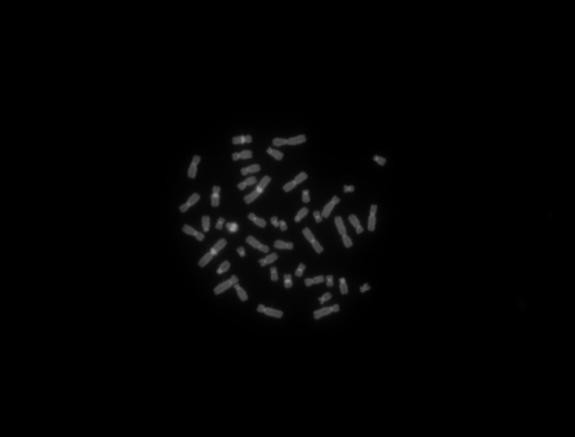

5、應(yīng)用實例:明場下,畫質(zhì)十分細膩,完全能滿足一般應(yīng)用。軟件具備,亮度,對比度,伽馬的參數(shù)的調(diào)整,通過調(diào)節(jié),都能得到比較滿意的照片。色彩還原方面稍顯不足,對于黑色的還原不是很理想,往往是有些發(fā)綠。熒光方面表現(xiàn)也很好,熒光模式下背景足夠黑暗,沒有明顯的噪點信號,彩色拍攝模式下,對紅色和綠色熒光的色彩還原準卻,但是對藍紫色和天藍色熒光的還原有待加強。建議拍攝熒光用單色模式,然后添加偽彩,熒光疊加。所以建議廠家增加這兩個功能。

熒光圖像:

熒光C帶2

Y微缺失DAPI藍紫